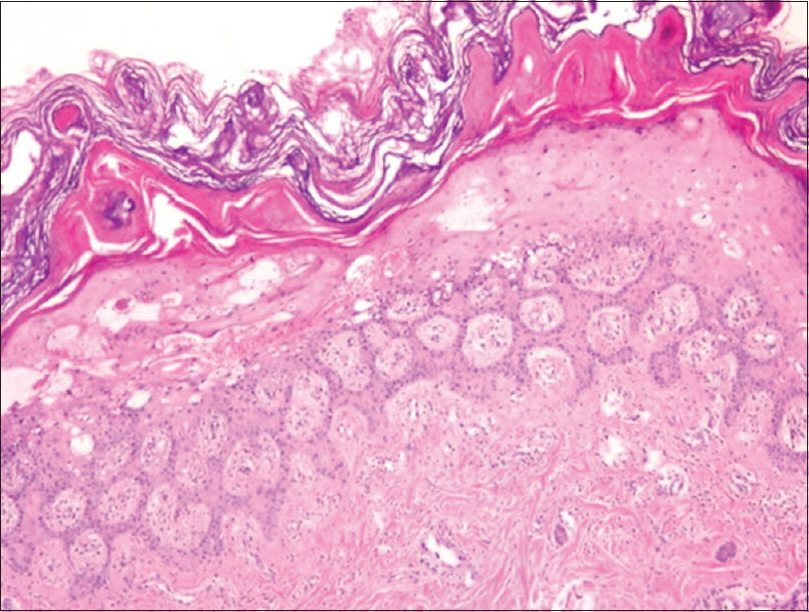

Histo acrodermatitis enteropathica

Pallor epidermis

Necrosis epidermis

Ballooning of epidermis

Psoriasiform hyperplasia